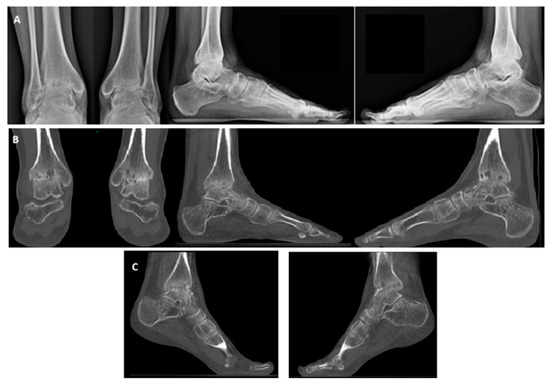

X-ray and weight-bearing CT revealed advanced osteoarthritis, characterized by anterior osteophytes, cysts in the medial malleolus region, and a valgus deformity of the hindfoot (Figure 3). Based on clinical and radiological findings, a decision was made to proceed with bilateral total ankle arthroplasty. Due to logistical considerations and in alignment with most of the literature, a simultaneous bilateral approach was chosen.

Figure 3. Hemophiliac patient suffering from bilateral ankle osteoarthritis. Preoperative images: X-rays (A), weight-bearing CT, AP and side view (B), and plantar flexion weight-bearing CT (C).